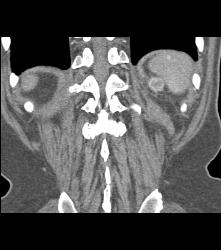

Recurrent Renal Cell Carcinoma Near Splenic Bed